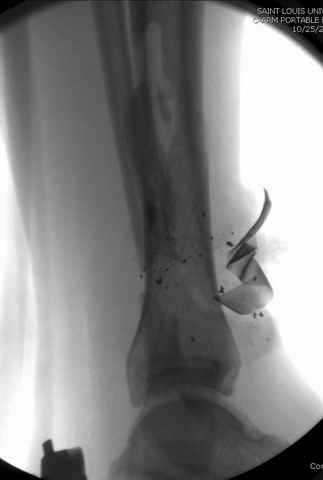

На снимках варианты фиксации малоберцовой:

№ 6-11 при pilon percutaneus fixation